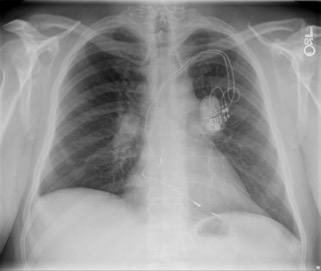

Diagnostic tests. Results of chest radiography (Figure 2) and computed tomography (Figure 3) revealed bilateral hilar adenopathy. The angiotensin-converting enzyme (ACE) level was found to be high. Results of a complete blood cell count, a basic metabolic panel, and liver function tests were normal, as were the erythrocyte sedimentation rate and the C-reactive protein level.

Figure 3. Computed tomography of the chest showing hilar adenopathy.